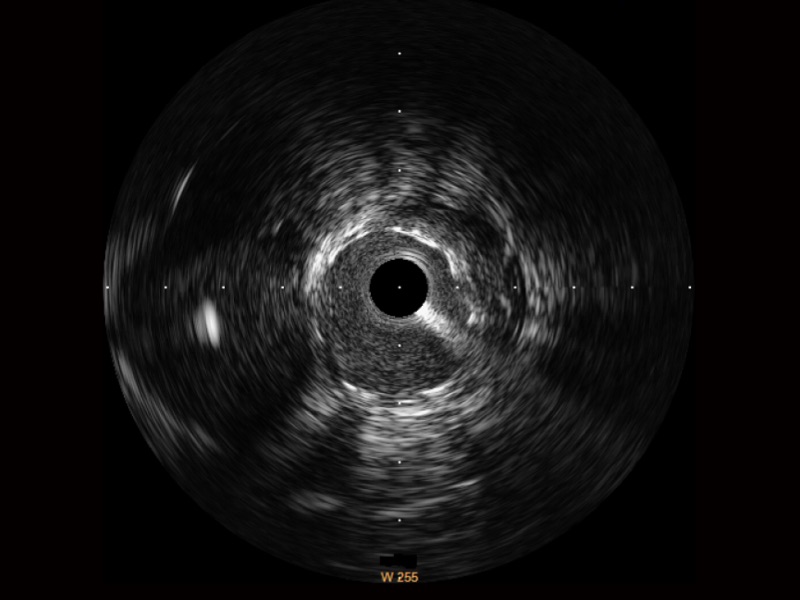

传统IVUS图像

对比传统IVUS导管成像,云顶集团官网宽频IVUS图像的近场支架梁显影更细腻,远场中膜外血管仍清晰可辨,兼顾远中近,兼顾分辨力与穿透深度